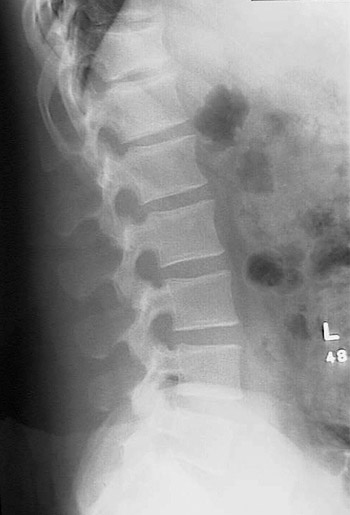

This is a normal lateral radiograph of the lumbar spine demonstrating the T12 vertebral body and L5 vertebral body and pedicle and spinous process.